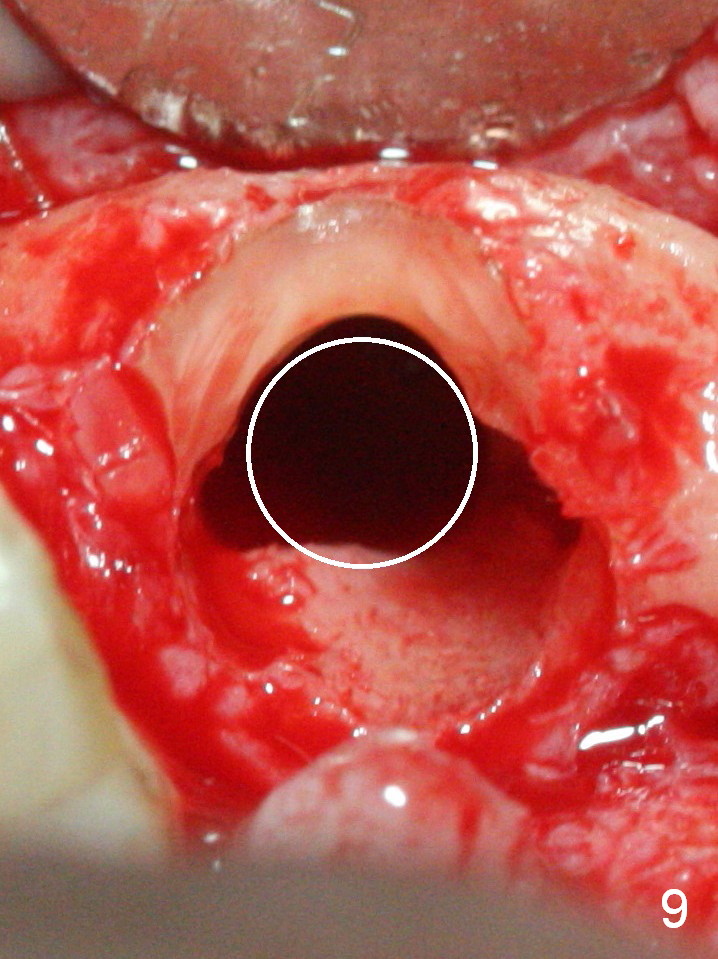

When the bridge is sectioned between #7 and 8, the tooth #6 is found non-salvageable (Fig.1).  Incision shows the atrophic buccal plate at #7 (Fig.2 arrowheads); to prevent the same feature from happening at #6 with thin buccal plate, the most buccal portion of the root is preserved (socket shield (Fig.2-4: *)).  The initial osteotomy is established in the palatal slope at #6 (Fig.5 circle) with 1.5 mm drill (Fig.6,7).  A portion of the root is visible in Fig.6 (arrowheads).  After sequential osteotomy with 2 mm, 3 mm (Fig.8) and 3.2 mm drills, a 4x15 mm implant is placed (Fig.10).  To accommodate the cross bite, the coronal portion of the implant (Fig.9 white circle) is positioned close to the socket shield.  It appears that the shield prevents the implant from encroaching the buccal plate.